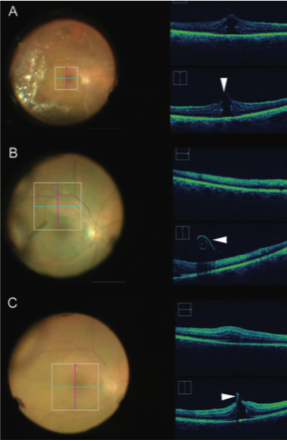

Figure 2. Image-guided feedback with intraoperative OCT during macular hole repair. Location of macular hole (arrowhead) with associated vitreomacular traction identified using pre-peel intraoperative OCT (A). After initiation of ILM peeling, a membrane edge with curled configuration consistent with ILM is easily visualized (arrowhead, B). After complete membrane peel, hole configuration has changed, and minimal residual ILM is visualized at the hole edge (arrowhead, C).

Similarly, intraoperative OCT has demonstrated that internal limiting membrane (ILM) peeling during macular hole surgery can cause changes in the geometry of the hole and in the outer retinal architecture (Figure 2). These changes may in turn have implications for anatomic success, defined as primary closure of the macular hole.21 In addition to the geometric changes that occur during ILM peeling, alterations in the EZ have been linked with the speed of anatomic normalization.22